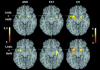

The progesterone derivative 4,16-androstadien-3-one (AND) and the estrogen-like steroid estra-1,3,5(10),16-tetraen-3-ol (EST) are candidate compounds for human pheromones. In previous positron emission tomography studies, we found that smelling AND and EST activated regions primarily incorporating the sexually dimorphic nuclei of the anterior hypothalamus, that this activation was differentiated with respect to sex and compound, and that homosexual men processed AND congruently with heterosexual women rather than heterosexual men. These observations indicate involvement of the anterior hypothalamus in physiological processes related to sexual orientation in humans. We expand the information on this issue in the present study by performing identical positron emission tomography experiments on 12 lesbian women. In contrast to heterosexual women, lesbian women processed AND stimuli by the olfactory networks and not the anterior hypothalamus. Furthermore, when smelling EST, they partly shared activation of the anterior hypothalamus with heterosexual men. These data support our previous results about differentiated processing of pheromone-like stimuli in humans and further strengthen the notion of a coupling between hypothalamic neuronal circuits and sexual preferences.